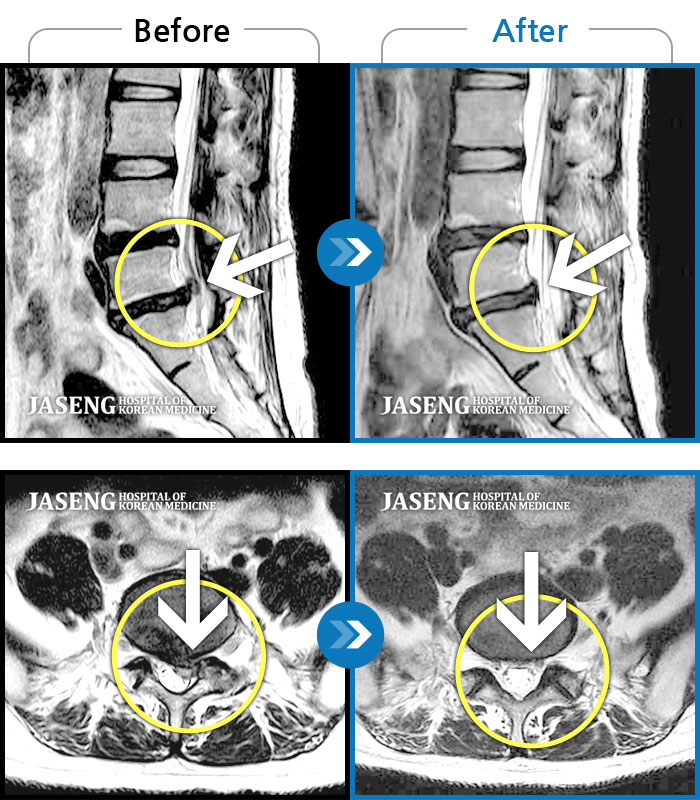

MRI 치료사례

허리 양측과 우측 둔부 통증, 좌측 하지 후면으로 저림